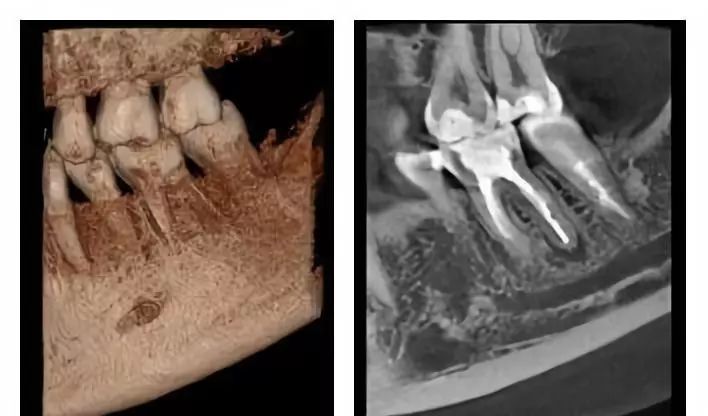

口腔CT是圍繞人體的一段容積螺旋式的采集數(shù)據(jù)。口腔CT與常規(guī)CT的本質(zhì)區(qū)別在于前者獲得的是三維信息,而后者獲得的是二維信息??谇籆T機(jī)提高了掃描速度,掃描覆蓋面廣,無間隙采集容積數(shù)據(jù),便于各種方式、各種角度的影像重建,且可以任意地、回顧性重建。視野選擇與圖像合成方面,口腔CT機(jī)比常規(guī)CT有著明顯的優(yōu)勢。它的空間分辨率高,對下頜骨、下頜神經(jīng)管、顳下頜關(guān)節(jié)解剖結(jié)構(gòu)、牙齒根管系統(tǒng)成像質(zhì)量更好。以下介紹三維口腔CT機(jī)的臨床應(yīng)用特點是什么?

通過三維重建并輔以軸位和其它層面圖像,便于醫(yī)生準(zhǔn)確了解埋伏牙,多生牙,囊腫,腫瘤等的形態(tài)、位置、鄰牙及臨近解剖結(jié)構(gòu)的關(guān)系。

4.神經(jīng)管定位功能

利用口腔CT機(jī)特有的神經(jīng)管著色功能,可以清楚標(biāo)識下頜神經(jīng)管與相鄰的重要解剖結(jié)構(gòu)的相鄰關(guān)系。如下頜阻生智齒拔出時,觀測神經(jīng)管與牙根的距離。